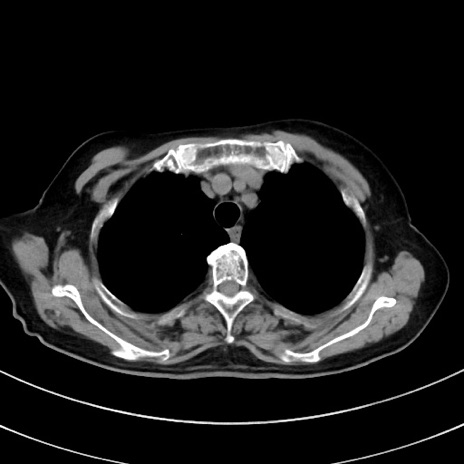

症例33(横断像)

【症例】70歳代 女性

【主訴】心窩部痛

【現病歴】延髄病変の精査・加療にて神経内科入院中。本日より心窩部痛あり。

【身体所見】右下腹部を中心に圧痛と反跳痛あり。